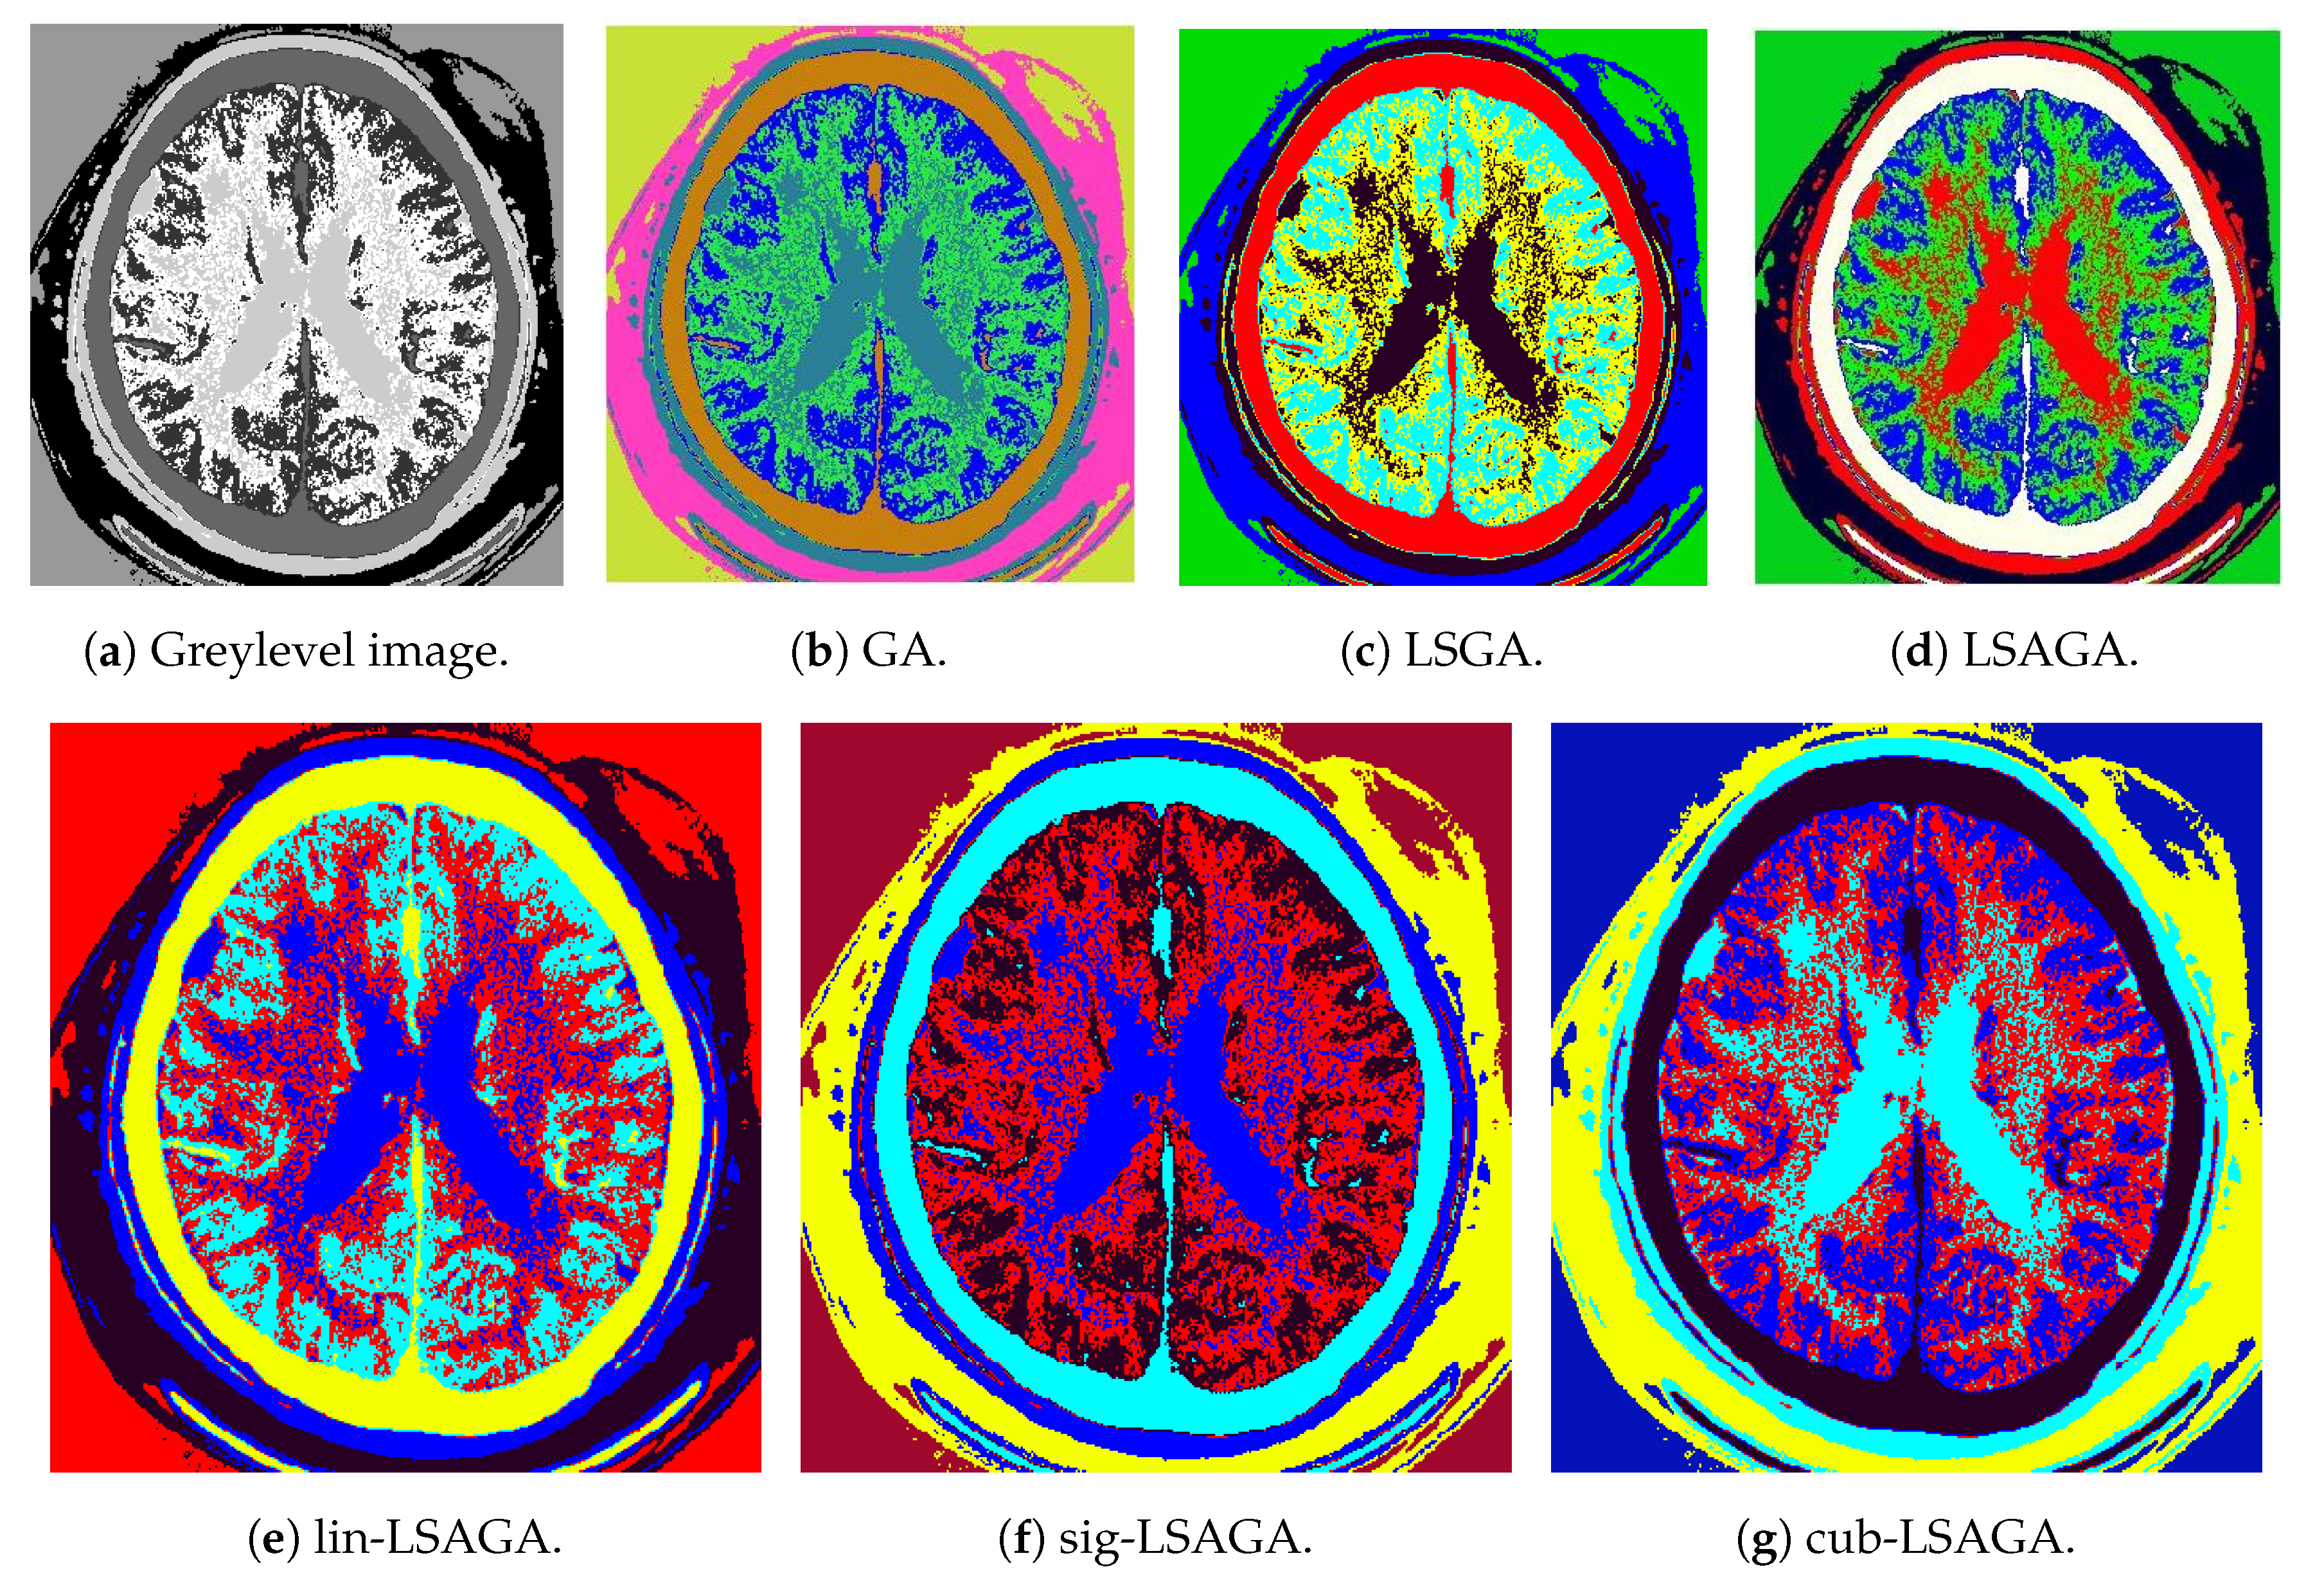

- Brains: This image is not very complex, as it has only six sub-regions. However, we can see that, in the case of the pseudo-colorization obtained by GA (Figure 9b), the colors used in the central part of the brain are two different shades of green, which can cause some visual confusion. This does not occur with the pseudo-colorizations obtained by the other methods.

- Two Brains: Concerning the images of the Two Brains, we can see that basic GA (Figure 10b) obtains a reasonably good visual separation between the sub-regions, presenting some confusion only with the colored regions in shades of red and pink in the central-left region of the image. In the pseudo-colorized image calculated by the LSGA method, there is also a confusion problem as well as in the basic GA. When analyzing Figure 10c, the central right region has a dark blue color very close to a region that was colored with black. These problems do not occur in the pseudo-colorization performed by the proposed technique with the addition of adaptive rules.